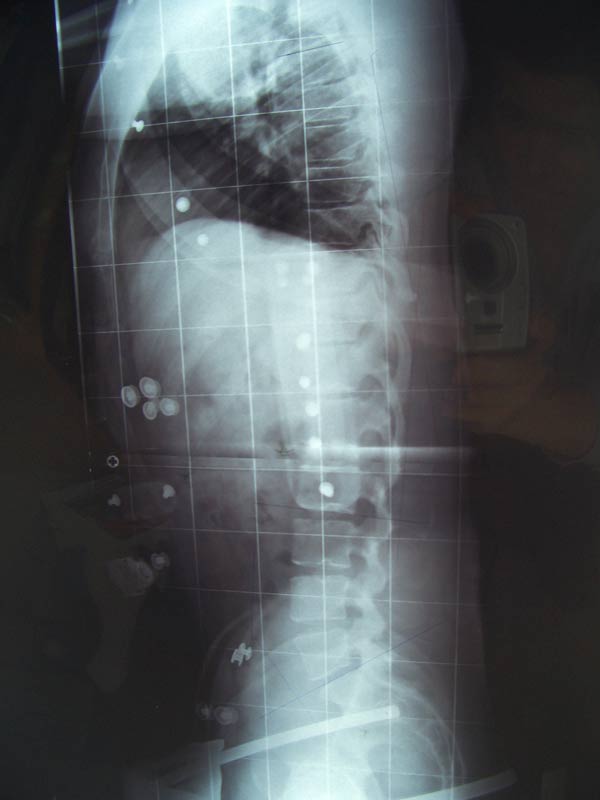

- Links: Ganzaufnahme

Rechts Oben: Banscheibenschäden in der HWS

Unten: Scheuermann und Knick zwischen LWS und Kreuzbein - TITEL.jpg (29.17 KiB) 14853 mal betrachtet

Auf meiner Ganzaufnahme erkennt man nun deutlich meine Fehlhaltung. Hyperlordose von 78°. Außerdem habe ich Scheuermann Typ II, einen Flachrücken und eine krumme HWS die schon mit 2 Bandscheibenschäden darunter gelitten hat.